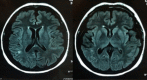

Patient and methods: We report the case of a 64-year-old woman with pneumococcal meningitis who developed parainfectious vasculitis causing ischaemic brain damage. Cerebral magnetic resonance imaging (MRI) confirmed the diagnosis. Clinical and radiological recovery after delayed addition of corticosteroid was achieved.

Discussion: This report shows that the onset of neurological deficits following pneumococcal meningitis can be caused by cerebral vasculitis. Underdosing with antibiotics and delayed adjunctive dexamethasone seem to favour this complication. There are no guidelines for treatment but high doses of steroids led to resolution in this case.